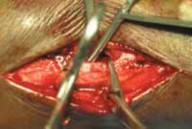

--- TECH FIG 2 • A. Cleaning the fracture site with a small curette. B An example of clamp placement across the fibular fracture site. Care is taken not to comminute the fracture spike. C. Lag screw placement, overdrilled with a 3.5-mm bit proximally. D. This is followed by drilling of the far cortex with a 2.5-mm drill. E. A neutralization plate is applied to the lateral surface of the fibula. F. Example of distal screw pen- G etration to be avoided. G. Wound closure. ANTEROMEDIAL APPROACH TO THE MEDIAL MALLEOLUS Exposure 1. The medial malleolus is approached via a gently curved anteromedial incision (

TECH FIG 3A

).

1. An incision is made parallel to the saphenous vein that is either concave anterior or concave posterior to allow visualization of the anteromedial joint.

TECHNIQUES A A

---

B

TECH FIG 3 • A. For a medial-side injury, the skin incision is curved about the medial malleolus. B. Fracture site is exposed and cleaned of hematoma and the talar dome is inspected for signs of chondral injury.

TECH FIG 4 • A. Reduction is achieved with a pointed reduction clamp. B. Guidewires for cannulated screws are placed across the fracture. 1. After dissection of the skin, the subcutaneous tissues should be carefully dissected to prevent injury to the saphenous vein and nerve.

2. With the dissection carried down sharply to the bone, the periosteum is elevated for 1 mm proximally and distally.

3. The fracture should be booked open to allow visual inspection of the talar dome for chondral injury.

4. The joint and medial gutter should be irrigated through the fracture for any loose hematoma or debris that may impede reduction (

TECH FIG 3B